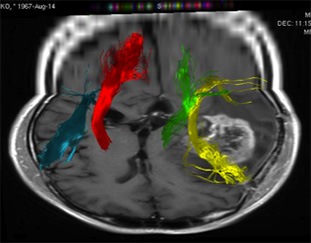

トラクトグラフィー Tractography

脳内の神経線維を詳細に調べ、脳腫瘍と重要な神経線維がどのような関係にあるのかを調べ、手術の時にこれらが損傷しないような手術プランを計画します。

(左図)ピンク色が脳腫瘍、緑色は運動の神経線維を示しています。

(右図)赤色は右の運動神経線維、緑は左の運動神経線維。黄色は言語機能の連絡をする神経線維を示しています。